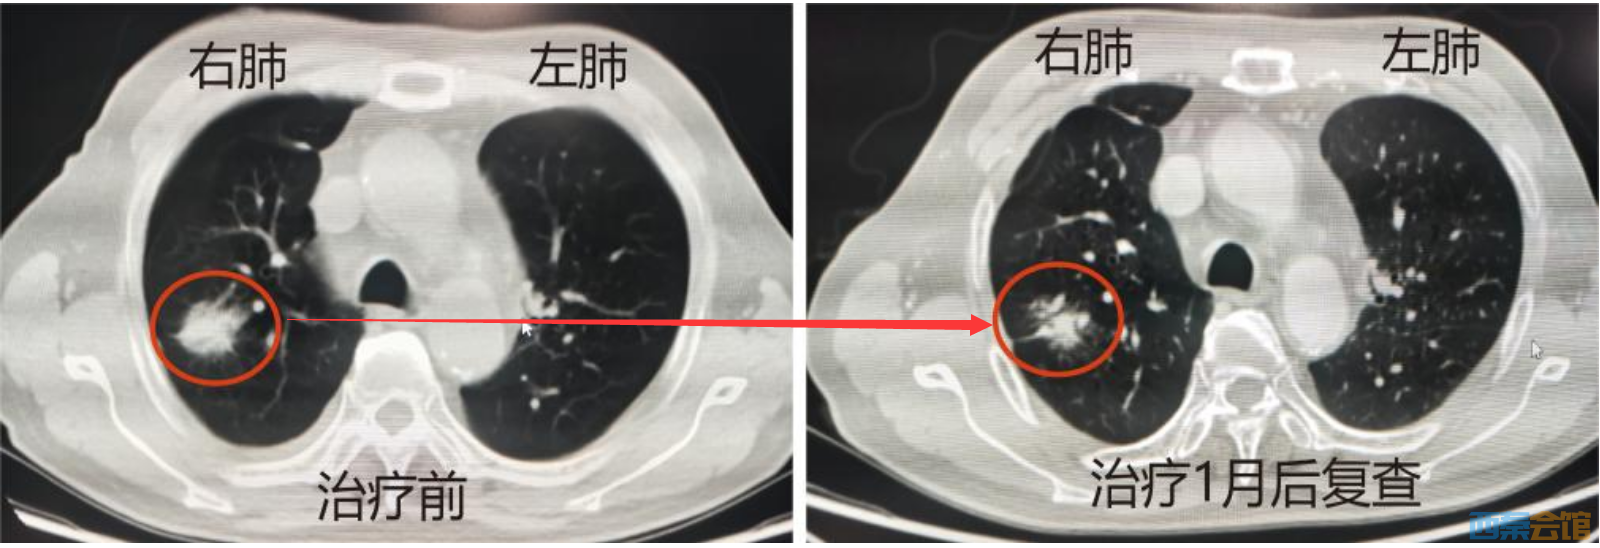

面对肺部肿瘤的诊断,宋大爷选择了勇敢。在医护团队的专业指导和详尽解释下,他理解并信任了这个治疗方案。2023719日,这个日子对宋大爷有着特殊的意义。在医疗团队的精心操作下,后装插植近距离放疗治疗过程仅用了45分钟。治疗期间和治疗后,他没有出现任何不适感。在治疗1个月后的复查结果更是给了宋大爷巨大的鼓舞CT显示右肺上叶肿块明显缩小。